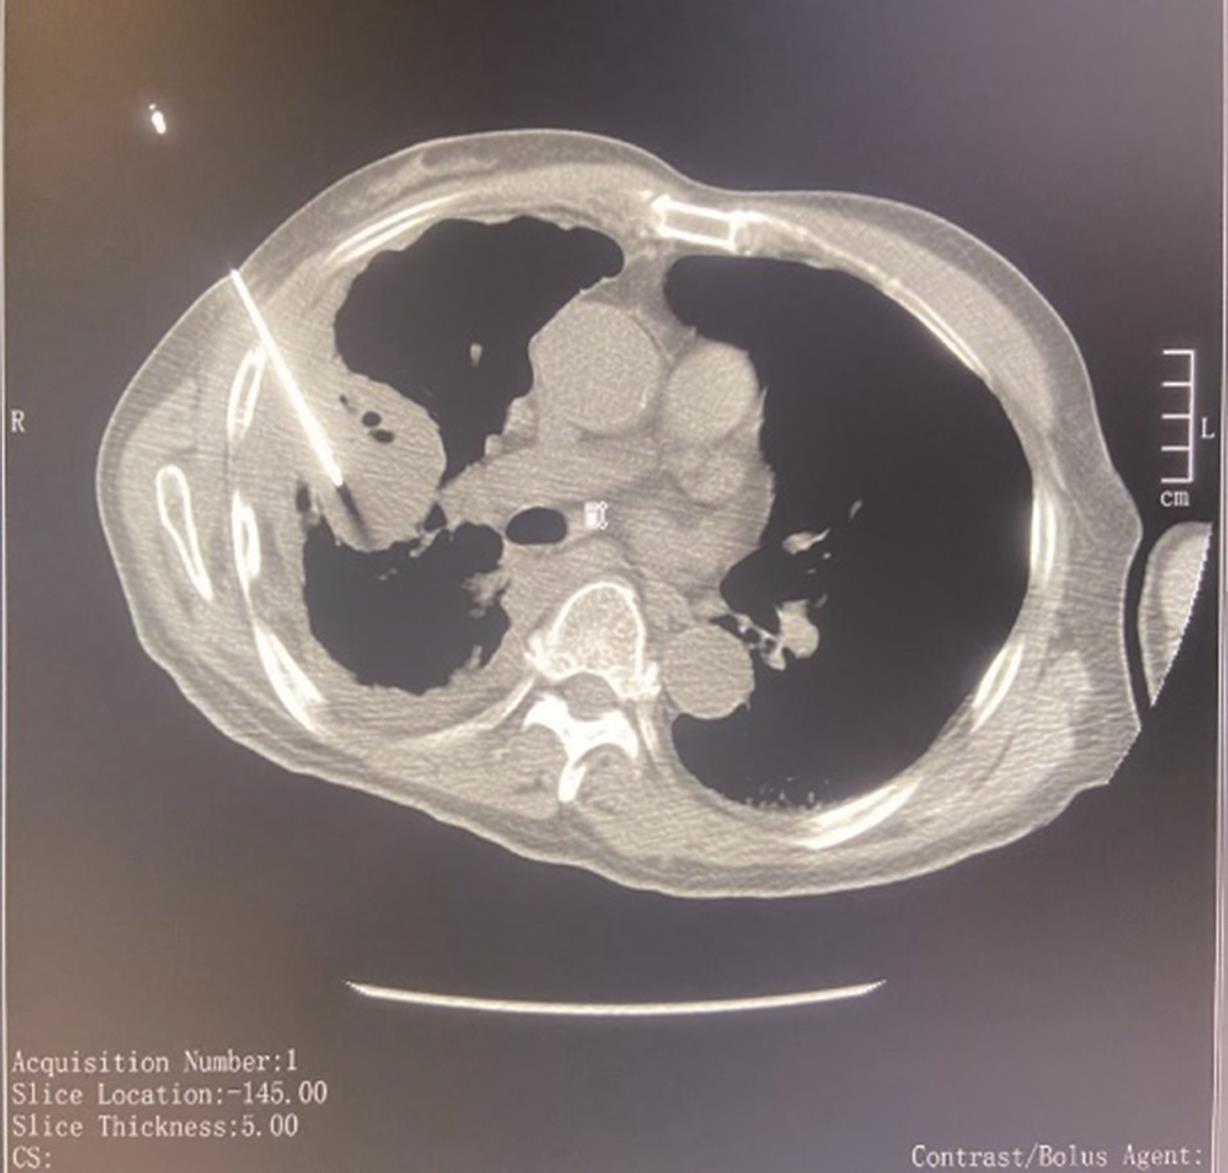

• 靶点靶线体表描记法在CT引导经皮肺穿刺活检术中的应用

2023, 48(9):1133-1137. DOI: 10.13406/j.cnki.cyxb.003328

摘要 (93) HTML (23) PDF 2.14 M (224) 评论 (0) 收藏

摘要:目的 旨在探讨靶点靶线体表描记法在CT引导经皮肺穿刺活检术中的技术要点及应用价值。方法 选取2021年8月至2022年4月进行肺穿刺活检的病例152例,随机分为A组(77例,采用靶点靶线体表描记法穿刺)和B组(75例,常规穿刺法),比较2组首次进针成功率、CT扫描次数、诊断准确率、术后并发症及手术时间以评估2种手术方法效果。结果 2组均穿刺成功并取得标本,穿刺成功率均为100%。首次进针成功:A组64例,B组62例,2组间无统计学差异(χ=0.005,P=0.941);CT扫描次数超标:A组18例,B组54例,2组间有统计学差异(χ=36.030,P<0.05);诊断准确:A组70例,B组68例,2组间无统计学差异(χ=0.003,P=0.959);咯血:A组12例,B组9例,2组间无统计学差异(χ=0.410,P=0.522);气胸:A组10例,B组11例,2组间无统计学差异(χ=0.090,P=0.764);手术时间:A组平均(19.88±4.47) min,B组平均(32.23±4.95) min,2组间有统计学差异(t检验,P<0.05)。结论 CT引导肺穿刺术中应用靶点靶线体表描记法简单易行,能准确指导CT引导肺穿刺术中穿刺角度的把握,减少术中CT扫描次数,值得在临床中推广。